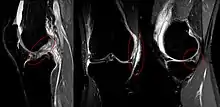

MRI images of Unhappy triad from left to right: ACL, MCL, medial meniscus.

In 1936, Cambell stated that an "impairment of the anterior crucial and medial ligaments is associated with injuries of the internal cartilage". In 1950, O'Donoghue described the unhappy triad as: (1) rupture of the medial collateral ligament, (2) damage to the medial meniscus and (3) rupture of the anterior cruciate ligament. O'Donoghue estimated the incidence rate in the traumatic sports knee to be 25%.[3]

In 1991, Shelbourne and Nitz questioned the validity of O'Donoghue's terrible triad study. A review of all arthroscopically confirmed acute injuries of second degree or worse to the ACL and MCL was performed. Of the 52 knees reviewed, 80% of group 1 had lateral meniscus tears and 29% had associated medial meniscus tears. None of the medial meniscus tears were isolated; medial meniscus tears were not present in the absence of a lateral meniscus tear.[3] From this study, it was concluded that the structures more typically involved in a triad were the anterior cruciate ligament, medial collateral ligament, and the lateral (not medial) meniscus.